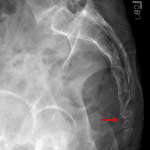

- Age-indeterminate mildly buckled fracture of the anterior cortex of the first coccygeal segment

- Coccyx fracture

Age-indeterminate mildly buckled fracture of the anterior cortex of the first coccygeal segment.

No joint malalignment.